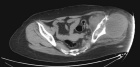

53 year old female with pelvic pain and fevers

History of left hip disarticulation due to a 2005 motor vehicle accident